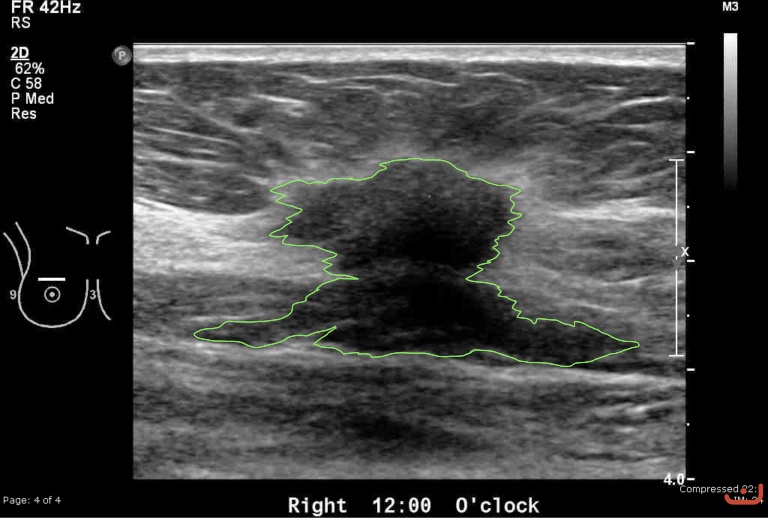

Case 39-G1

Malignant solid mass

Friday, 22 May 2015

199.93 KB (768 x 518 px)